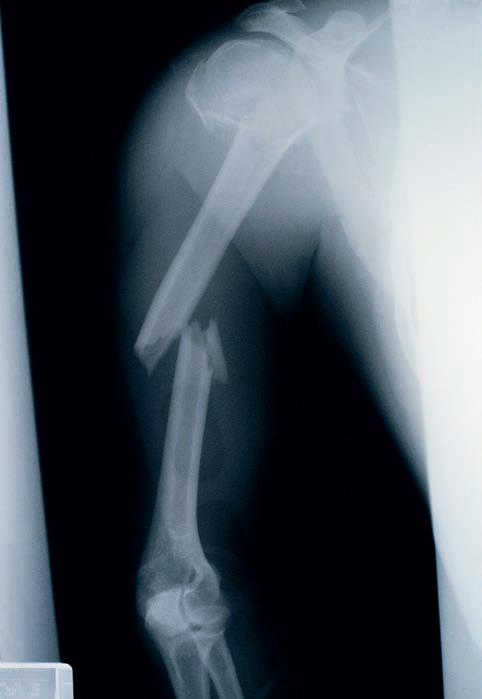

Tøft med gips I sommer brakk jeg armen.

Jeg måtte på sykehuset og få gips.

Dagen etter var Didrik og jeg ved Tunevannet.

Jeg glemte at jeg hadde gips og hoppet ut i vannet.

Gipsen ble våt, og jeg måtte på sykehuset og få ny gips.

Gjett om jeg var populær!